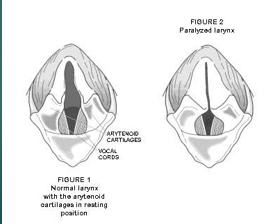

Laryngeal paralysis

Loss of motor function of the larynx

Causes a narrowing of the larynx so is harder for their air to move through

Most commonly seen in large breed dogs

Laryngeal paralysis can be caused by ..

Polyneuropathy

Trauma

Iatrogenic - neck surgery

Hypothyroidism

Neoplasia - mass on the larynx or on the nerve

Polyneuropathy